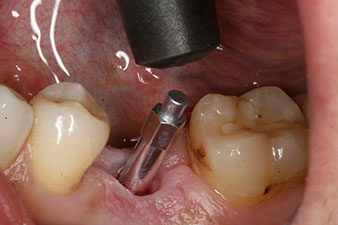

Después de la cicatrización de los tejidos blandos, se volvió a determinar la estabilidad del implante antes de continuar con el tratamiento protésico.

Los dos valores eran prácticamente idénticos y se encontraban en la transición del área media a la alta; en este punto cabe reseñar que el valor más bajo sirve siempre como referencia para establecer el tratamiento adecuado.

Con ello, fue posible documentar una correcta osteointegración y una estabilidad biológica suficiente, lo que permitió realizar una conformación en la misma sesión.